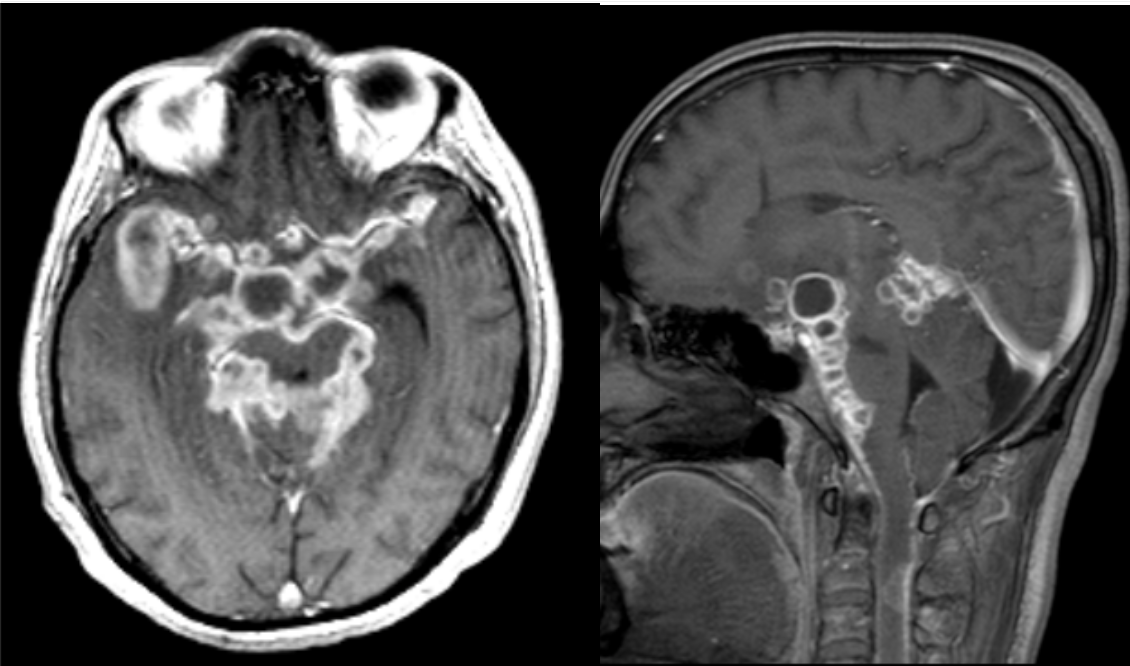

28 year-old developed cranial nerve deficits and soon became encephalopathic and died.

Tuberculosis meningitis

Imaging